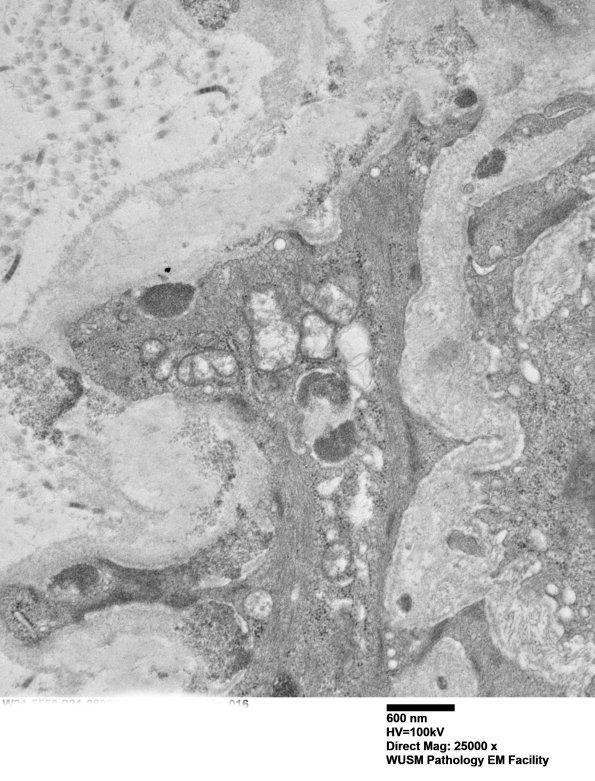

11E5E Several GOMs involving a separate part of the vessel wall. (electron micrograph)